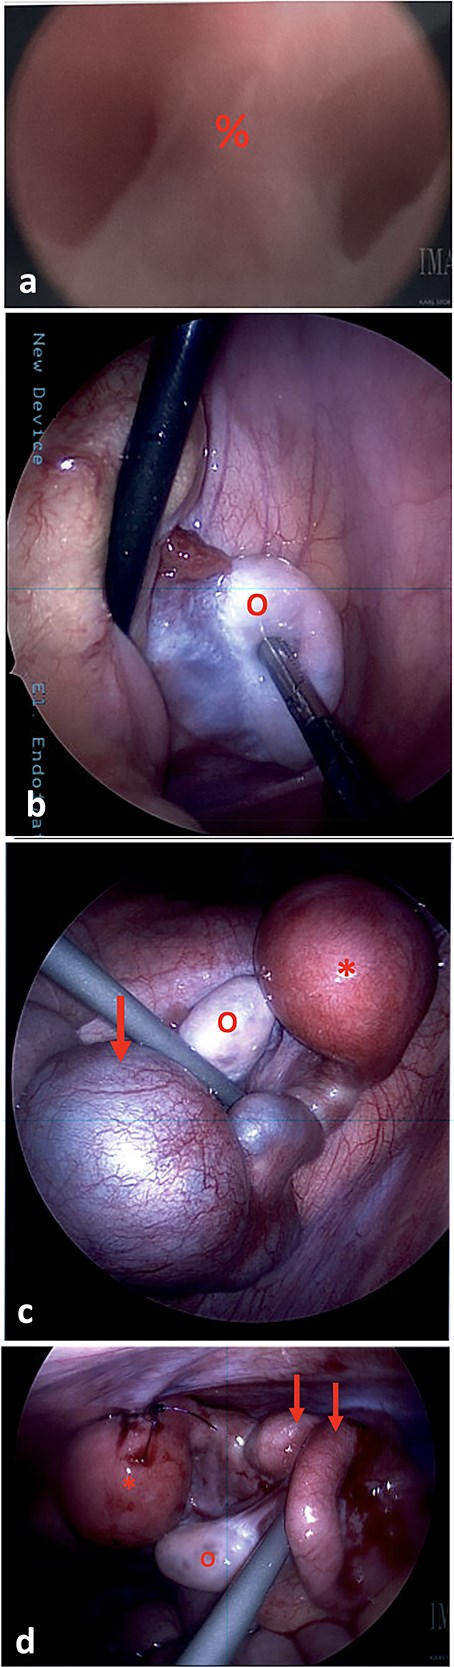

(a) On vaginoscopy, a central septum (%) was noted, suggestive of a longitudinal vaginal septum or hemi-vaginas. (b) Laparoscopic photograph showing the left ovary (o) located in the left lower pelvis, not attached to any tubal structure. (c) Laparoscopic photograph demonstrate a right-sided hypertrophic uterus (*), significantly dilated and firm due to retained blood, and a markedly dilated and tortuous right fallopian tube (arrow). The right ovary appeared normal (o). (d) The uterine dome (*) was sutured to the abdominal wall. The right fallopian tube was decompressed after aspiration (arrows).

During diagnostic laparoscopy, 50 ml of clear serous fluid was aspirated from the pelvic cul-de-sac. A left ovary was present in the left lower quadrant, but no left sided uterine or tubal structures were identified (Fig. 2b). On the right side, a hypertrophic hemiuterus was visualized, significantly dilated and firm due to retained blood (hematometra) (Fig. 2c). The right fallopian tube was markedly dilated and tortuous with a cystic dilation at the mid portion consistent with hematosalpinx. The right ovary appeared normal. No intrabdominal vaginal structures were noted.

The cystic segment of the fallopian tube was laparoscopically punctured and 60 ml of dark blood was aspirated. The uterine fundus was separately punctured and 40 ml of dark blood was aspirated, consistent with hematometra. A 10Fr silicone Foley catheter was inserted into the uterine dome using a hook cautery device. The balloon was inflated, and the uterus was affixed to the abdominal wall with 2-0 PDS sutures (Fig. 2d).